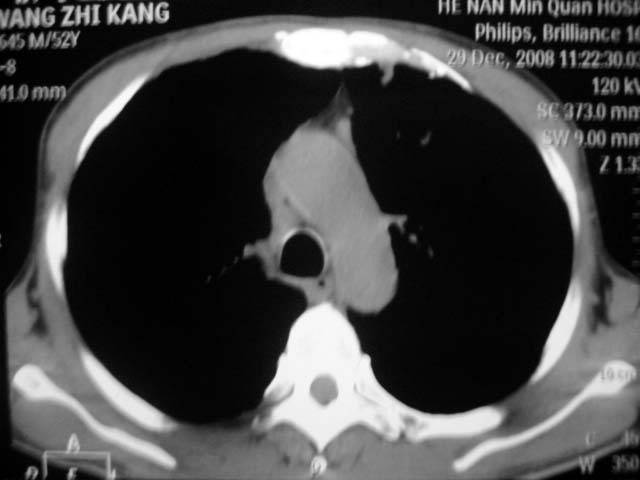

男,52岁,发热2月,糖尿病史。

抗结核治疗irpz方案,血糖未治疗,空腹15.9左右。症状无好转,左胸痛。

复查ct

2、双肺见多发片状及结节状高密度影,大多数病灶中心均见“空泡征”。

3、纵隔内淋巴结肿大。

结果:两肺继发性肺结核并曲霉菌感染。